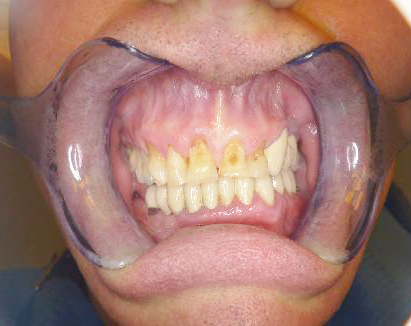

Případ 7: Rekonstrukce horních frontálních zubů

Celokeramika

Pacient trpěl nevratným vážným poškozením zubů způsobeným především příliš agresivním čištěním (silný tlak na zubní kartáček), ošetřující lékař měl podezření i na bruxismus (skřípání zubů). Bylo zapotřebí zvolit dostatečně trvanlivé a odolné řešení. Proto jsme zvolili variantu celokeramických solo korunek v tomto provedení: lithium-disilikátová korunka v redukovaném tvaru, pokrytá tenkou vrstvou keramické hmoty pouze na vnější, viditelné straně, to vše individuálně dobarveno a glazováno.

Ošetřující lékař: MUDr. Roman Michejda